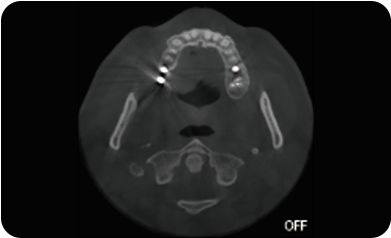

临床样片